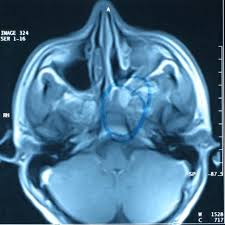

MR → Yumuşak doku detayında üstün